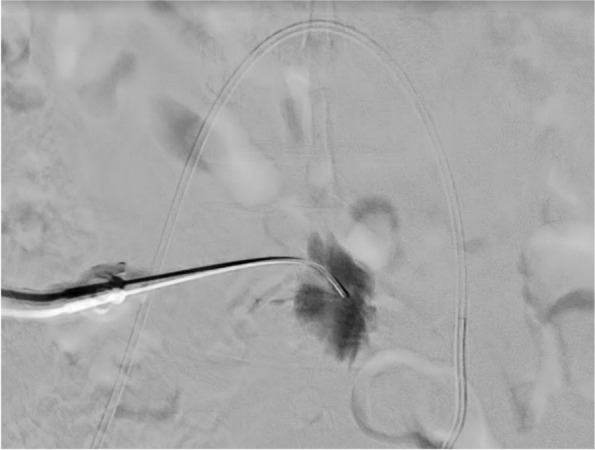

Methods: A 51 year old woman presenting with menorrhagia due to uterine fibroids was referred to interventional radiology for embolization. She was allergic to most opiates and had previously become agitated with IV midazolam, resulting in termination of a previous attempt at embolization. Thus, a combination of three analgesic modalities was used: intraarterial ropivacaine in the uterine arteries, superior hypogastric nerve block with ropivacaine, and intravenous acetaminophen. The patient underwent successful embolization and reported only intermittent pain of 1-2 out of 10 intensity.